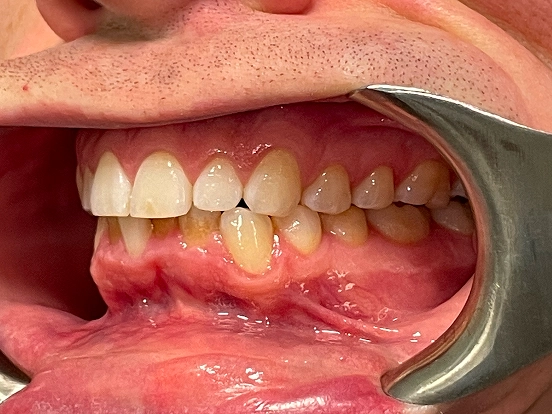

Invisalign DT

DT’s transformation with Invisalign is a perfect example of how advanced orthodontic technology can deliver incredible results. The clear aligners gradually corrected the alignment and bite issues, creating a straighter, healthier, and more attractive smile—all without noticeable brackets or wires.